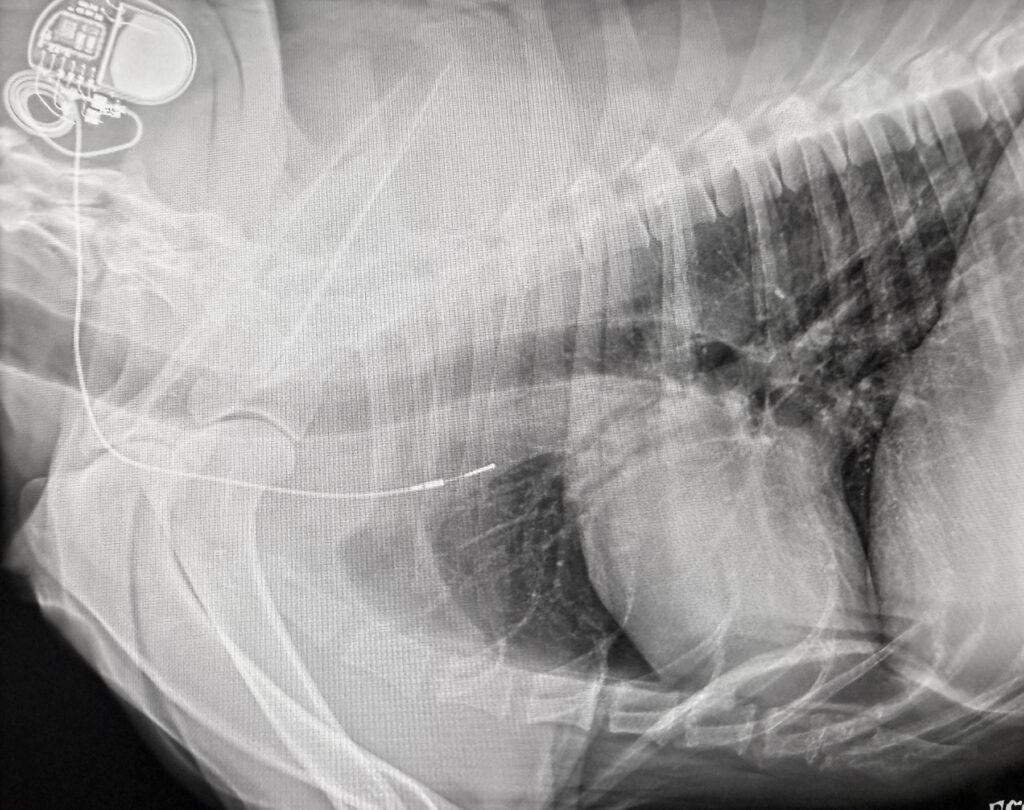

Digital Radiology / X-rays: Our digital X-ray system allows us to quickly and safely capture clear images of your pet’s bones, organs, and tissues. This non-invasive imaging helps us diagnose fractures, monitor organ health, and detect conditions early — all with minimal stress to your pet.

ECG: Our in-house ECG provides a detailed look at your pet’s heart rhythm and electrical activity. The results are reviewed by a board-certified cardiologist, giving us expert insight into your pet’s cardiac function and helping guide accurate, tailored treatment plans. This collaboration ensures your pet’s heart health is closely monitored with both precision and compassionate care.

Ultrasound / Echocardiogram: Our in-house ultrasound allows us to quickly evaluate your pet for common concerns, providing fast insights when time is of the essence. For more advanced needs, such as detailed abdominal imaging or echocardiograms, an ultrasound specialist visits our hospital to perform comprehensive studies. This combination ensures your pet receives both timely, practical assessments and the highest level of diagnostic expertise when needed — all in a caring, stress-minimized environment.